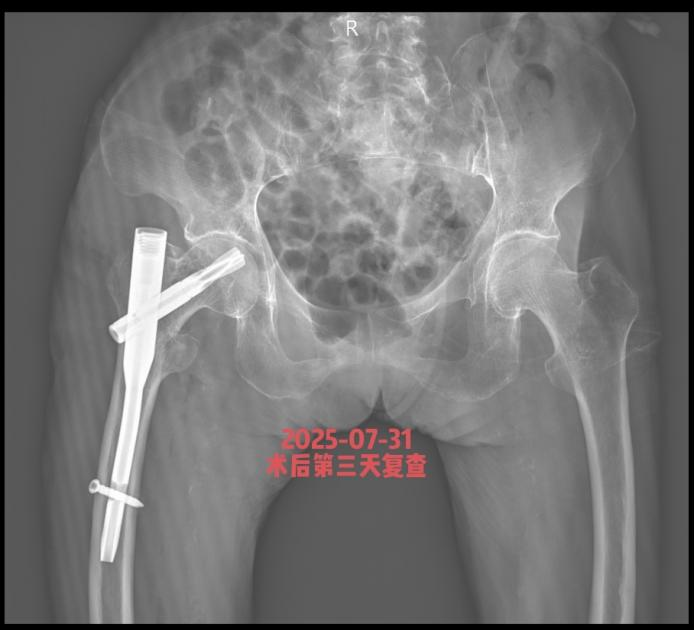

近期,85岁李奶奶,因摔倒致右股骨粗隆间粉碎性骨折,来我院就诊。

患者高龄,并发高血压、冠心病及肺部基础疾病,我院骨科团队迅速联合内科主任、麻醉科医师进行多学科会诊,评估病情,最终确定在腰麻下行右股骨粗隆间骨折闭合复位髓内钉内固定手术方案。安庆市第一人民医院骨科何流教授率领王亮主治医师通过 3 个小切口完成骨折复位与固定,手术顺利,术后恢复良好,术后5天李奶奶可以翻身自行坐起,目前在助行器辅助下部分负重行走。